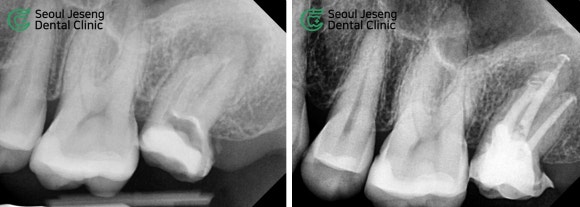

먼저 정밀 검사를 통해 치아 상태를 꼼꼼히 살펴보았습니다.

일반 평면 엑스레이에서 보기에도 뿌리 끝 염증 사이즈가 상당합니다.

신경치료용 CT를 촬영하니 상악동으로 염증이 파급되려는 상태였고, 기존 신경치료의 흔적도 확인할 수 있었습니다.